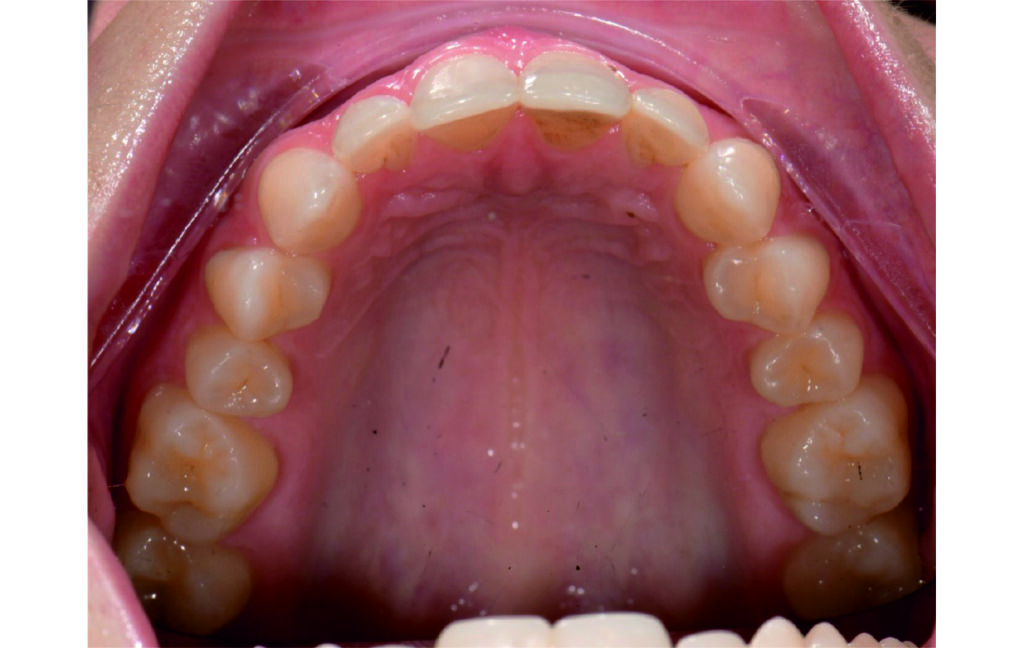

Angle Class II 2mm on the right, Angle Class II 2mm on the left, light mandibular asymmetry to the right, lower central line 1mm to the right, upper central line 1,5mm to the left, 1mm overjet and overbite. Sagittal asymmetry of upper dental arch. Light crowding upper and lower frontal segments, severe attrition of posterior teeth, night bruxism. Normal sagittal position of both jaws, high angle case, steep mandibular ramus,excessive lower facial height, open bite tendency.

The case initially presented as a moderate Class II on the right and a Class II tendency on the left, with tapered dental arches and an anterior open bite extending to tooth 26 in segment II.

In segment I, the open bite reached up to the first premolar.

A 1.5 mm deviation of the upper dental midline to the patient’s left was noted, along with a slight mandibular midline shift to the right, likely due to asymmetrical mandibular growth observed in the facial structure. Severe mesial rotations of teeth 16 and 26 were evident in the initial records. As derotation of 16, 26, 17, and 27 progressed up to aligner 16, the premolars in segments I and II moved distally, resulting in a bilateral Class I relationship, as intended in the initial treatment plan.